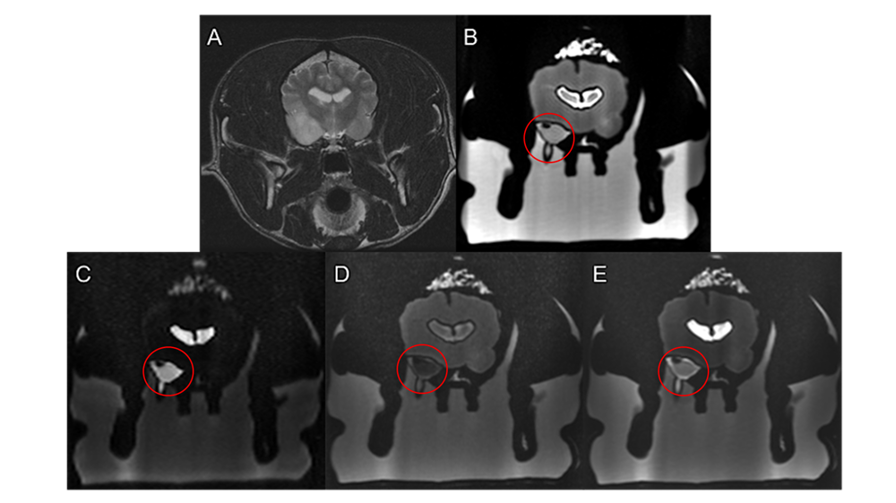

MRI scan of the dog (A) and the printed phantom with various analyses highlighting the tumor in red circle (B,C,D,E)

Several versions of the model were produced using Stratasys' Digital Anatomy solution to allow for CT and MRI imaging. Axial3D handled the intricate segmentation, combining MRI data for soft tissue structures like ventricles and the tumor with CT data for bone and muscle detail. To maximize training potential, the team added a second, artificial tumor to the model for biopsy practice purposes.

Initial scans of the printed models revealed remarkable fidelity between the printed anatomy and Charlotte’s original imaging data. Hounsfield Unit (HU) values from the CT scans of the model closely mirrored those of the real patient, demonstrating material accuracy and confirming that the prints could be used for realistic, scan-compatible planning.